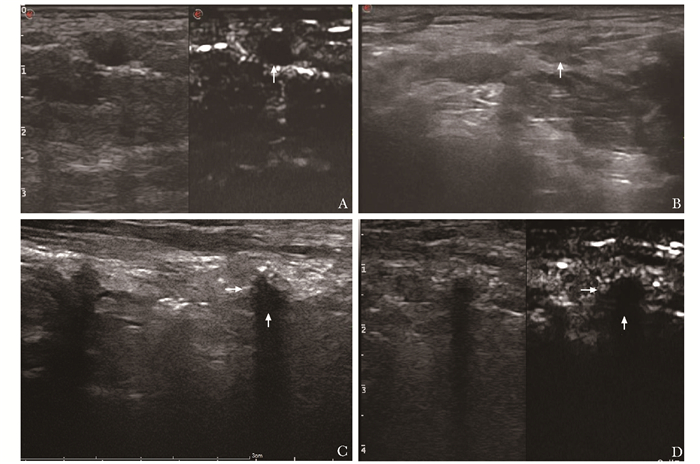

结果  共35例(46个MLNs病灶)符合纳入和排除标准的患者入选本研究。术前超声造影显示,20个MLNs为不均匀灌注(包括1个液化淋巴结),26个为均匀灌注。术后2~7 d复查超声造影显示,灌注缺损区边界较术后1 h更清晰,灌注缺损区体积比术后1 h明显增大230.40(78.03,361.17)mm3比130.62(43.06,253.66)mm3P<0.05。所有患者对PLA均耐受良好,无颈部血肿及活动性出血、感染、气管食管损伤等并发症发生。平均随访(56.7±8.9)个月,无原位淋巴结复发病例。与术前比较,末次随访时消融后病灶最大径0.00(0.00,0.00)mm比7.35(5.70,9.63)mm,P<0.05、病灶体积0.00(0.00,0.00)mm3比95.59(32.82, 169.01)mm3P<0.05均显著缩小。术后1、3个月及末次随访时消融后病灶体积缩小率分别为100(40.381,100)%、100(96.110,100)%和100(100,100)%。

Results  A total of 35 patients (46 cervical MLNs) meeting the inclusive and exclusive criteria were enrolled in this study. Preoperative CEUS showed that 20 MLNs were heterogeneously perfused (including 1 liquefied lymph node), while 26 MLNs were homogeneously perfused. During 2-7 d after PLA, CEUS showed that the boundary of the perfusion-defect area was clearer than that of 1 h after the operation, and the volume of the perfusion-defect area was significantly larger than that of 1 h after the operation230.40(78.03, 361.17)mm3 vs. 130.62(43.06, 253.66)mm3, P < 0.05. All patients tolerated well to PLA without neck hematoma, active bleeding, infection, tracheal esophageal injury, or other complications. The mean follow-up was (56.7±8.9)months, and there was no case of lymph node recurrence in situ. The maximum diameter 0.00(0.00, 0.00)mm vs. 7.35(5.70, 9.63)mm, P < 0.05 and the lesion volume 0.00(0.00, 0.00)mm3 vs. 95.59(32.82, 169.01)mm3, P < 0.05 at the last follow-up after ablation were significantly reduced compared with preoperation.